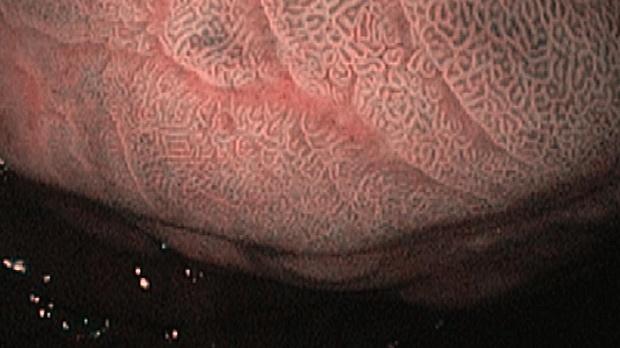

Появление ультратонких гастроскопов с высоким разрешением и технологией NBI (оптического узкоспектрального режима) компания OLYMPUS сделала возможной гастроскопию экспертного уровня под местной анестезией, без наркозных рисков.

Ультратонкие гастроскопы GIF-XP170N и GIF-XP190N с параметром оптики Close Focus, который позволяет приближаться к слизистой на минимальную глубину резкости до 2 мм, обеспечивают качество изображения, сопоставимое с аппаратами экспертного класса.

В Центре Экспертной Эндоскопии, г. Симферополь с июня 2018 с помощью этих эндоскопов выполнено более 1000 эндоскопических исследований, с полным соблюдением критериев качества ESGE. Среднее время исследования составило 14мин. 51с. Все исследования выполнялись с предварительной подготовкой желудка, применением водяной помпы и СО2-инсуффлятора, фото- и видеодокументацией.

Использование в ежедневной рутинной практике современных ультратонких эндоскопов высокого разрешения с технологией оптического узкоспектрального режима (NBI® OLYMPUS™) под местной анестезией позволило полностью обеспечить соответствие критериям качества выполнения эндоскопических исследований, определенным ESGE. Данный метод комфортен для пациента под местной анестезией, безопасен, является простой и удобной альтернативой ЭГДС под седацией, что особенно важно в амбулаторных условиях.